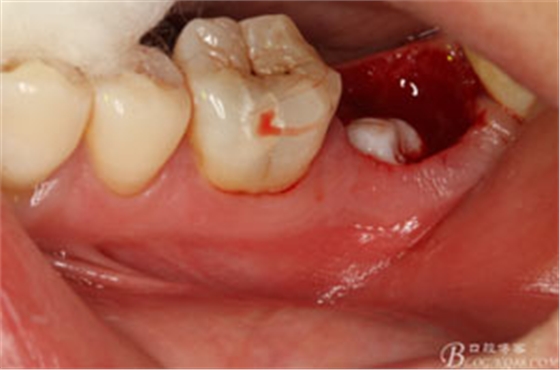

患者、申xx、女、40歲,主訴:左側(cè)下頜后牙牙齦紅腫不適數(shù)月。??茩z查:37合面有一開髓孔。髓腔內(nèi)有一暫封小棉球,探針髓腔底部出血,疑為在外院治療導(dǎo)致底穿。x線片檢查:37頰側(cè)齦下有一枚多生牙,多生牙壓迫頰側(cè)牙根及牙體組織大量吸收。

圖2.37牙冠基本完好,松動Ⅰ度。合面有一開髓孔被棉球覆蓋,頰側(cè)牙齦輕度紅腫。